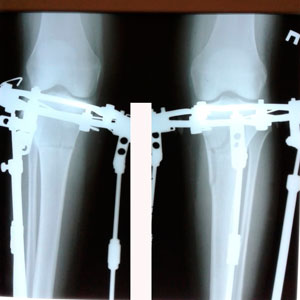

в процессе исправления деформации

image-27-05-20-05-53-11.jpg